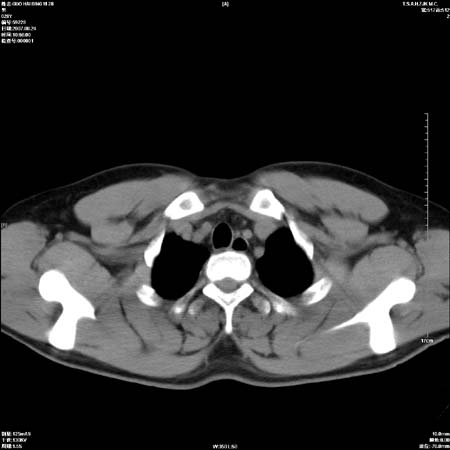

男性,28岁,体检发现左肺病变,患者只有背部隐痛感,哀哉,真不忍心下诊断啊。

左肺门区软组织肿块,左肺上叶支气管开口消失,纵隔内见肿大淋巴结,考虑左中心型肺部,可以做纤支镜取病理确认.

左肺肺门区肿块影,分叶明显,左肺上叶支气管开口受压,纵隔内见肿大淋巴结,考虑左中心型肺癌。